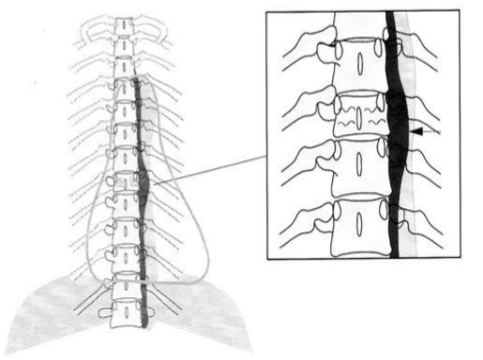

What are owl faces?

on AP projections all vertebrae should have an owl face

Eyes - pedicles, you should always see two of them

Beak - spinous process

Easiest to see in the lumbar spine but can be used throughout